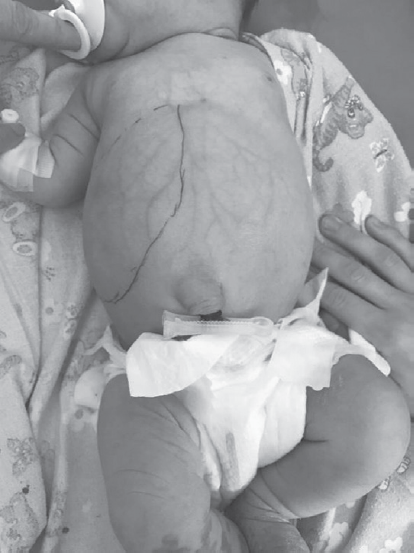

Hemangiomas are the most frequent tumors of childhood age. In the first year of life their prevalence is 10–12%. Among premature children, the prevalence of hemangiomas correlates with the degree of prematurity. Liver hemangiomas are a wide range of benign vascular formations that can acquire both malignant course and capable of spontaneous regression. Small-sized hemangiomas generally do not require specific treatment and proceed asymptomally. Large-sized formations can cause life-threatening conditions such as severe thrombocytopenia with coagulopathy (Kazabah–Merrit syndrome), anaemia, tumor hemorrhage, spontaneous and traumatic tumor breaks, heart failure associated with intra-tumor bypass of blood flow, abdominal compression syndrome, severe hypothyroidism. Diagnosis of this pathology is carried out on the basis of a set of data of medical imaging, laboratory diagnostics and clinical picture. This review presents key points of general classification, the most characteristic diagnostic signs, as well as basic algorithms of treatment of liver hemangiomas in newborns and children of the first year of life. There are also described 2 clinical cases of newborns with giant liver hemangiomas, which were examined and treated in the pathology department of newborns and infants of Perinatal Center of St. Petersburg State Pediatric Medical University with a description of the peculiarities of the course of each of them.